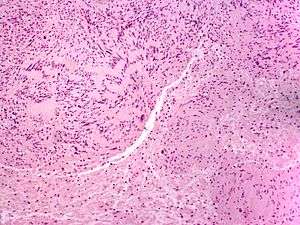

A neuroma /njuːˈroʊmə/ (plural: neuromata or neuromas) is a growth or tumor of nerve tissue.[1] Neuromas tend to be benign (i.e. not cancerous); many nerve tumors, including those that are commonly malignant, are nowadays referred to by other terms.

Neuromas can arise from different types of nervous tissue, including the nerve fibers and their myelin sheath, as in the case of genuine neoplasms (growths) like ganglioneuromas and neurinomas.

The term is also used to refer to any swelling of a nerve, even in the absence of abnormal cell growth. In particular, traumatic neuroma results from trauma to a nerve, often during a surgical procedure. Morton's neuroma affects the foot. Neuromas can be painful, or sometimes, as in the case of acoustic neuromas, can give rise to other symptoms.